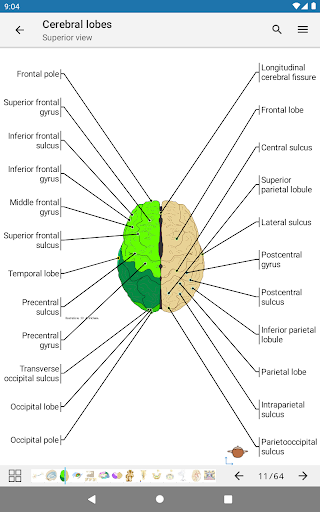

e-Anatomy memiliki lebih dari 26.000 gambar yang berisi serangkaian gambar dalam tampilan aksial, koronal, dan sagital serta radiografi, angiografi, gambar diseksi, bagan anatomi, dan ilustrasi. Semua gambar medis diberi label dengan cermat, lebih dari 967.000 label tersedia dalam 12 bahasa termasuk Terminologia Anatomica Latin.

- Gulir set gambar dengan menyeret jari Anda

- Perbesar dan perkecil

- Ketuk label untuk menampilkan struktur anatomi

- Pilih label anatomi berdasarkan kategori